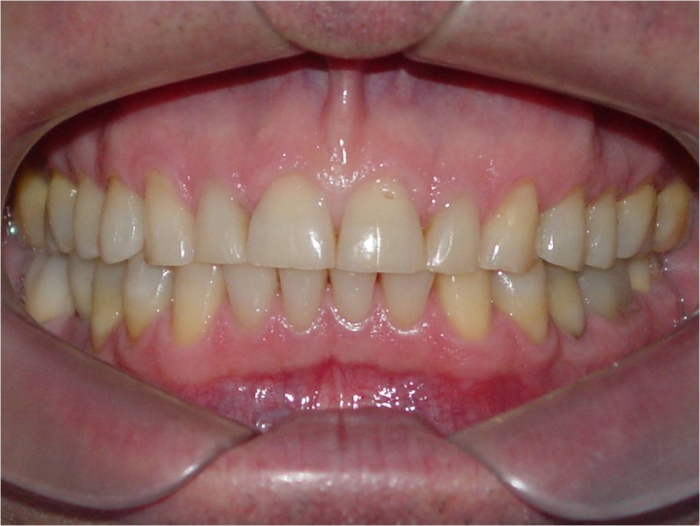

Mordida após a remoção do aparelho